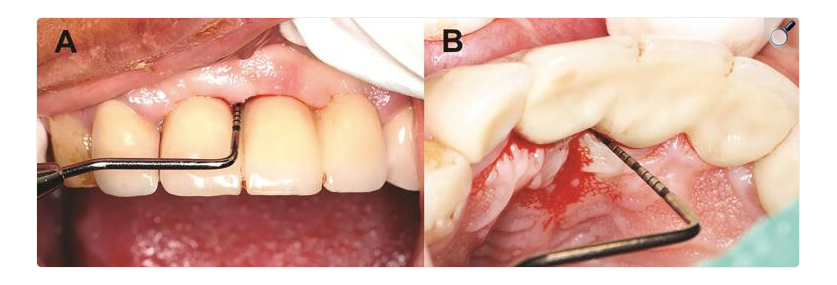

Mucozita periimplantară este caracterizată prin inflamația țesuturilor moi care înconjoară implantul dentar, fără a fi asociată cu pierdere osoasă dincolo de remodelarea inițială post-inserare. Clinic, aceasta se manifestă prin semne inflamatorii la nivelul mucoasei periimplantare, precum eritemul, edemul și sângerarea la sondare. Din punct de vedere biologic, mucozita reprezintă un răspuns inflamator reversibil, determinat de acumularea biofilmului microbian la nivelul suprafeței implantului și al componentelor protetice.

Sursa foto: PMC7536094

Importanța mucozitei periimplantare rezidă în potențialul său de progresie. Studiile recente subliniază faptul că, în absența unei depistări precoce și a unei intervenții adecvate, inflamația limitată inițial la țesuturile moi poate evolua către periimplantita, cu afectarea osului de susținere. Această tranziție nu este bruscă și nici întotdeauna însoțită de modificări clinice evidente, ceea ce face ca monitorizarea sistematică să fie un element-cheie în practica implantară.

Din punct de vedere terapeutic, abordarea mucozitei periimplantare se bazează pe controlul eficient al biofilmului microbian. Literatura actuală susține faptul că piatra de temelie a tratamentului profesional constă în distrugerea mecanică și îndepărtarea biofilmului prin instrumentație atentă, utilizând instrumente manuale sau dispozitive cu ultrasunete, adaptate suprafețelor implantare. Intervențiile trebuie realizate cu precauție, pentru a evita alterarea suprafeței implantului și traumatizarea țesuturilor periimplantare.